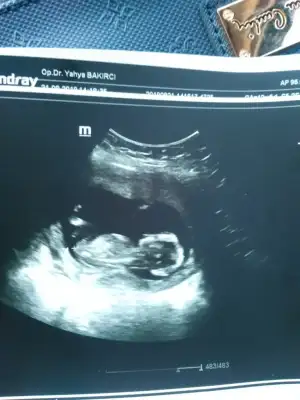

Bacakları kapalı uyuyordu uyandiramadi doktor söyleyemedi 16 haftadayimNub için 11 yada 12 hafta olmalı minnoş baya buyuk sanırım dr sölemedimi 21 hafta takviminiz kız diyorum görüntüsüne![]()

Takviminiz 21 hafta görünüyor 11 yada 12 hafta usg paylaşırmısınızBacakları kapalı uyuyordu uyandiramadi doktor söyleyemedi 16 haftadayim